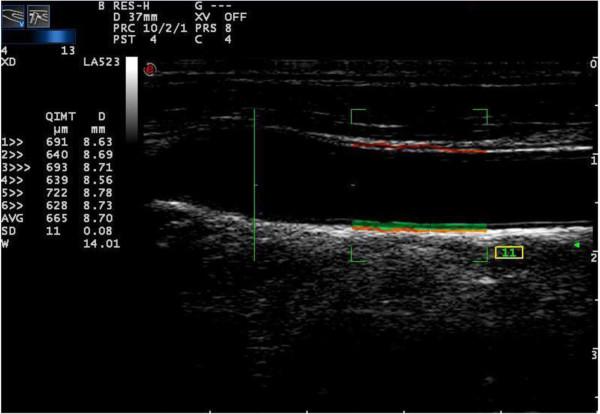

Ninety-one subjects were assigned into two groups; a diabetes group and a control group. Structural and functional changes in the common carotid arterial wall were investigated by quality intima-media thickness (QIMT), quality arterial stiffness (QAS), and X-strain analysis with a Mylab Twice ultrasound instrument. The relationships among variables between the two groups were analyzed in this study.

There was no significant difference in carotid IMT (626.5 ± 169.1 μm vs. 568.5 ± 122.6 μm, P = 0.1506) between two groups. Pulse wave velocity (PWV) and stiffness index (β) were remarkably greater (8.388 ± 3.254 m/s vs. 7.269 ± 1.332 m/s; 12.51 ± 14.16 vs.9.279 ± 2.871), while compliance coefficient (CC) decreased significantly in the diabetes group (0.802 ± 0.3094 mm2/Kpa vs. 0.968 ± 0.3992 mm2/Kpa) (P < 0.05). The displacement difference of radial (RD-D), longitudinal (LD-D) and rotation (ROT-D) directions were significantly different between two groups' comparison (P = 0.0212, P = 0.0235 and P = 0.0072, respectively). The time of circumferential peak strain difference (CS-DT) and the time of radial peak strain rate (RSR-T) were found to be significantly different between the two groups (341.9 ± 77.56 ms vs. 369.0 ± 78.26 ms, P = 0.0494; 142.7 ± 22.43 ms vs. 136.2 ± 30.70 ms, P = 0.0474). CS-TD and RSR-T were also found to be positively correlated with CC value (r = 0.3908, P < 0.005 and r = 0.3027, P = 0.0326, respectively). Finally, PWV was negatively correlated with CC with (r = -0.6177, P < 0.001).